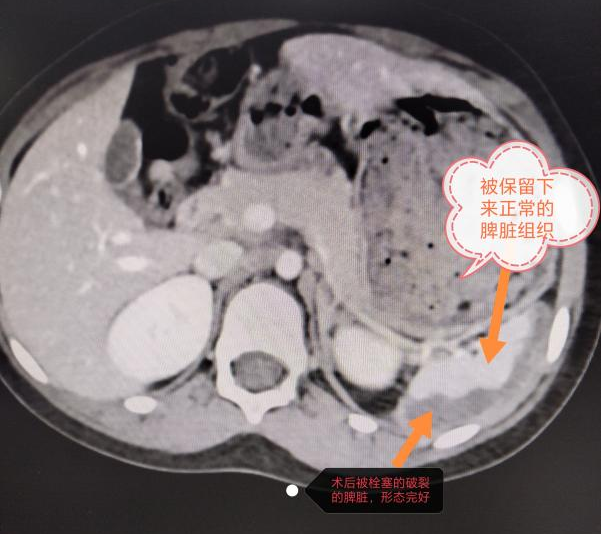

术后复查CT,脾脏被保留,出血已止

介入栓塞止血,以最短时间、最小的创伤止血,同时保住了一部分剩余脾脏功能,术后小女孩身上不留任何疤痕或针孔的痕迹,这对于一个7岁的女孩来说是非常重要的。由于脾脏有很强的再生能力,若干年后女孩的脾脏将恢复到正常人水平,几乎找不到任何手术痕迹,充分体现了介入治疗的精准和微创。